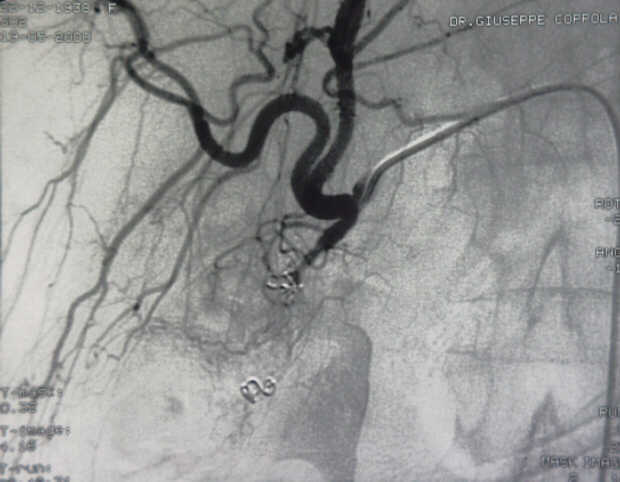

Diagnosis: Angiography

Giuseppe Morelli Coppola, Raffaella Niola, Franco Maglione

Unità Operativa di Radiologia Vascolare ed Interventistica, Azienda Ospedaliera "A. Cardarelli". Napoli, Italy